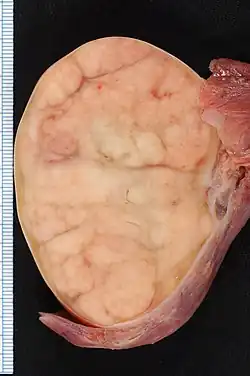

The cut surface of the tumour is fleshy and lobulated, and varies in colour from cream to tan to pink. The tumour tends to bulge from the cut surface, and small areas of hemorrhage may be seen. These areas of hemorrhage usually correspond to trophoblastic cell clusters within the tumour.[5]

Gross pathology of seminoma

Gross pathology of seminoma -

Orchidectomy specimen showing seminoma

Orchidectomy specimen showing seminoma -